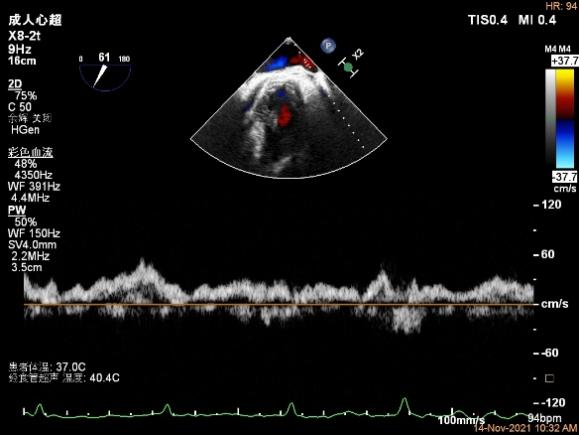

X-plane:下夹子尝试捕获靠近AC区脱垂瓣叶

将第二个夹子置于第一个夹子内侧尽量靠近,并调节Rotate呈尽量平行关系

成功抓捕内侧残余脱垂区域瓣叶